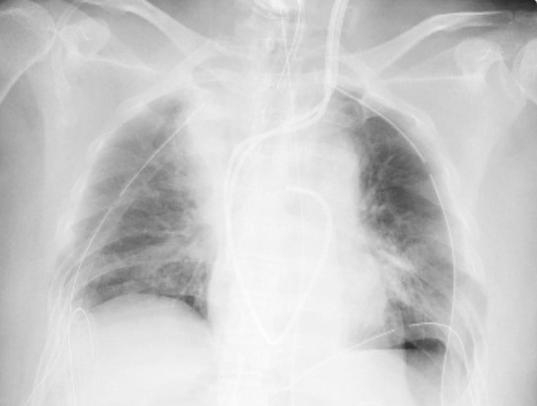

負責執刀的京都大學醫學部附屬醫院呼吸器外科主任伊達洋至表示,因為患者的肺臟組織變得脆弱,容易出血,所以單是止血就花了好幾個小時。手術前女病患的肺部X光檢查顯示,兩側肺臟呈現白色,而不能發揮功能,但手術後,肺臟在X光片上已呈黑色,可正常發揮功能。